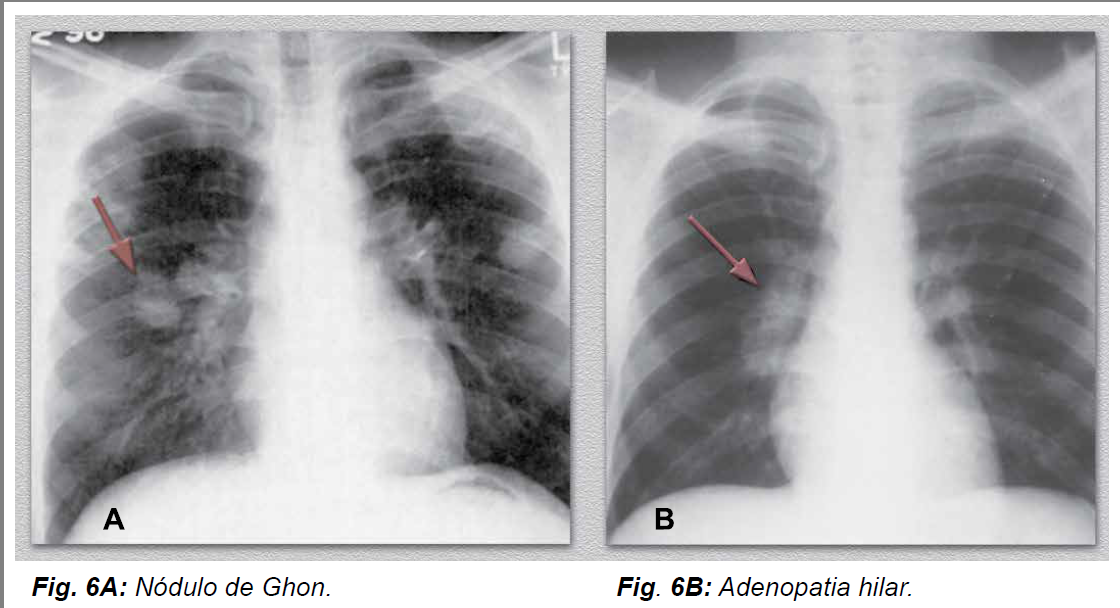

O que é o nódulo de Ghon?

É o foco pulmonar granulomatoso onde “tudo começou”, ou seja, o local do pulmão que contém o granuloma de onde foi inoculado o BK.

Como o nódulo de Ghon aparece no rx de tórax?

A maioria não é visualizado, porém quando grande, pode ser visto como um nódulo pulmonar solitário, podendo ou não estar calcificado.

Qual o achado de raio x de tórax a primoinfecção pode ter?

Nódulo pulmonar solitário (nódulo de Ghon) e adenopatia hilar unilateral.

*A associação do nódulo de Ghon com adenopatia satélite é chamada de complexo primário/de Ranke.